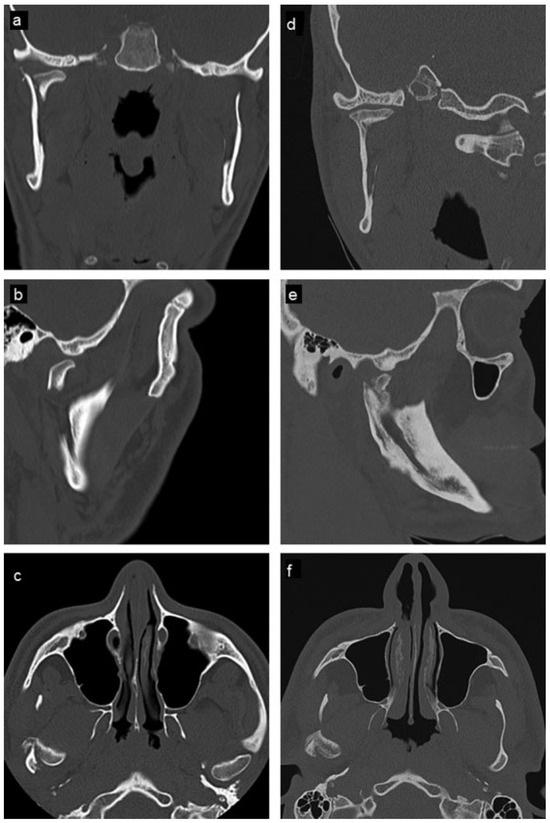

Orbitozygomatic fractures are one of the most common maxillofacial injuries encountered. This study aims to investigate and review the management and complications of orbitozygomatic fractures at the Royal Brisbane and Women’s Hospital (RBWH). Specif...